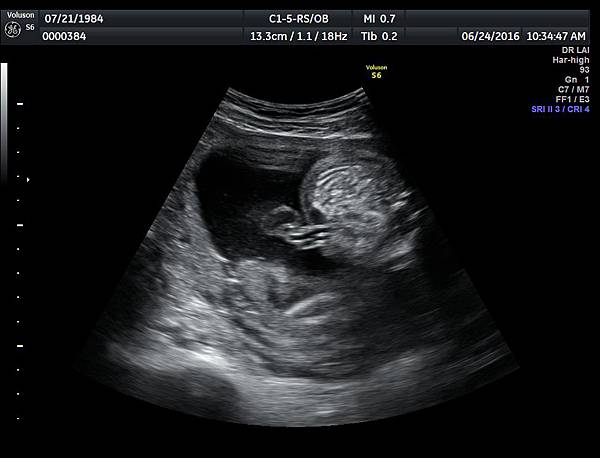

6月24日在我的診所,我幫一位懷孕22週31歲的孕婦看高層次超音波,發現胎兒的腸子很白,形狀也特別的怪( 附圖 1~12 ),我建議她做進一步相關的檢查,包括抽羊水檢查等等。